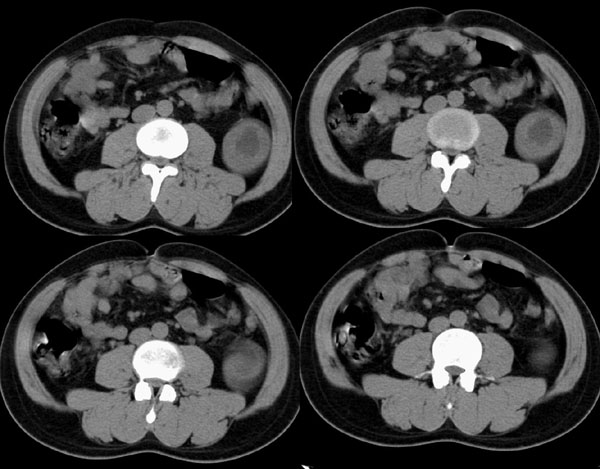

左侧肾盂、肾盏扩张,肾盂输尿管移行部突然狭窄,未见明显占位及高密度结石影,体检发现,考虑:先天性肾盂输尿管移行部狭窄。(原因多方面,有先天缺陷造成移行部结构异常或因为迷走血管、纤维索条引起肾盂输尿管的压迫扭曲所致。)大剂量ivp或肾盂造影有助于显示输尿管狭窄部位及形态。

就是简单的左肾盂积水,原因很可能是肾门部的血管压迫所致,建议做多期增强

左肾积水(原因待查),不排除左肾盂输尿管移行部迷走血管压迫所致可能。